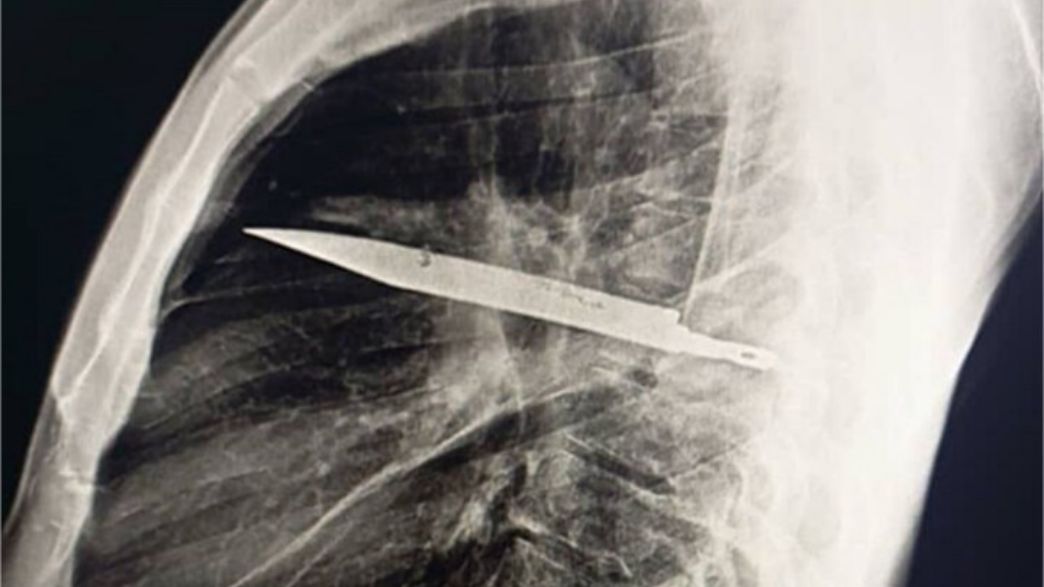

הרופאים, שלא הצליחו להבין את מקור או סיבת ההפרשה, שלחו את המטופל לבצע צילום רנטגן – וגילו ממצא בלתי ייאמן: להב ענק תקוע בתוך בית החזה שלו.

לפי הדו"ח הרפואי, שפורסם ב-National Library of Medicine, הלהב חדר דרך השכמה הימנית של המטופל, ופספס בנס את כל האיברים החיוניים. מאחר שבבית החולים שבו טופל בעבר לא היו אמצעי דימות מתקדמים, הלהב לא התגלה והמשיך לשבת בגופו במשך שמונה שנים בלי לגרום כאבים.